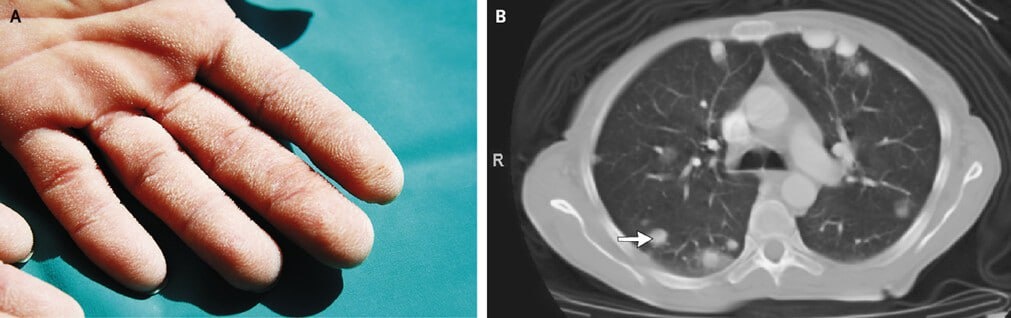

А он, Иван, начал смеяться. Не смог справиться с нахлынувшими чувствами, впервые встретив смерть так близко. «Бархатная рука». Признак рака легкого или желудка…

симптом "бархатной руки"

Он машинально схватил женщину за ладонь, поглаживая ее, вспоминая то давнее ощущение жуткой бархатистости кожи, какой не должно быть на гладкой и плотной коже ладони здорового человека. Посмотрел в глаза своей визави и понял, что это ведь и не бабка вовсе… А женщина средних лет. Просто она очень, очень худая. И вот-вот упадет в обморок – то ли от удивления, то ли от возмущения его беспардонным поведением.

Это была карцинома легкого. Кашель мучал ее давно, но она привыкла не обращать на него внимания, как и многие курильщики, что не встают по утрам без одышки и необходимости избавиться от мокроты, прокашляться как следует, перед тем как сделать первую утреннюю затяжку и тем продолжить бесконечный цикл, что ведет к инвалидности, а зачастую и к смерти. Боль в ноге возникла из-за метастаза, который проник в бедренную кость.

Эта сказка не могла закончиться хорошо. К сожалению, диагноз был установлен верно, подтвержден на компьютерной томографии легких и при помощи тонкоигольной аспирационной биопсии. Метастаз в бедро увидели при проведении сцинтиграфии костей. Пациентку успели направить на химиотерапию – увы, тщетно. Ее не стало через несколько недель.

«Бархатная ладонь», которая обычно является проявлением паранеопластического синдрома при злокачественной онкологии, стала как бы безмолвным свидетелем конца и никак не помогла пациентке своевременно получить медицинскую помощь – но женщина ведь за ней и не обращалась. А стоило бы. Тогда, когда кашель стал изматывающим и постоянным. Тогда, когда начала повышаться без какой-либо причины температура. Тогда, когда ночная потливость пробуждала от ощущения, что мокрая не только футболка, но и постельное белье. Тогда, когда заболела нога, начал стремительно падать вес…